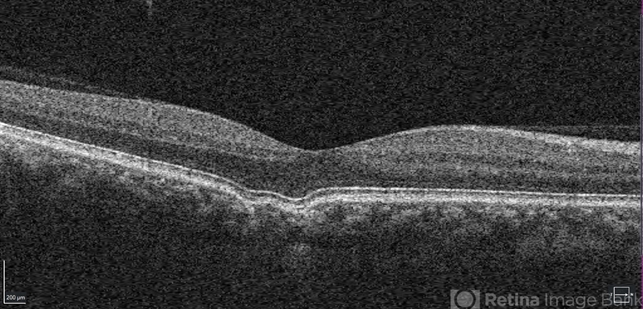

- Focal choroidal excavation.